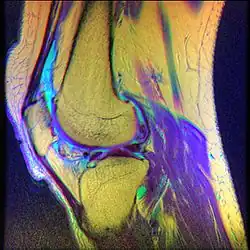

| Diagnostic method | MRI |

- Magnetic Resonance Imaging (MRI) – to observe cartilage condition and assess deterioration